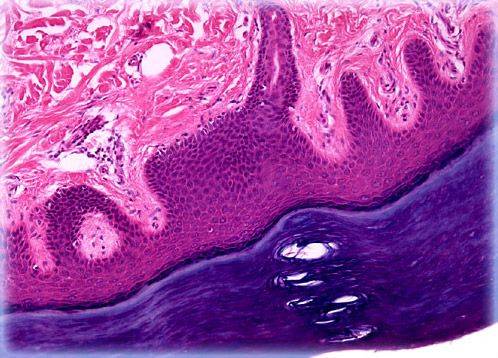

Plantar skin is the integument that covers the soles of the feet of humans and other primates. Similar to the skin found along the palms, plantar skin is relatively thick, greatly keratinized, hairless, and filled with a dense collection of sweat glands, which is the reason why the feet and hands are often the first parts of the body to get sweaty when someone is nervous or anxious.